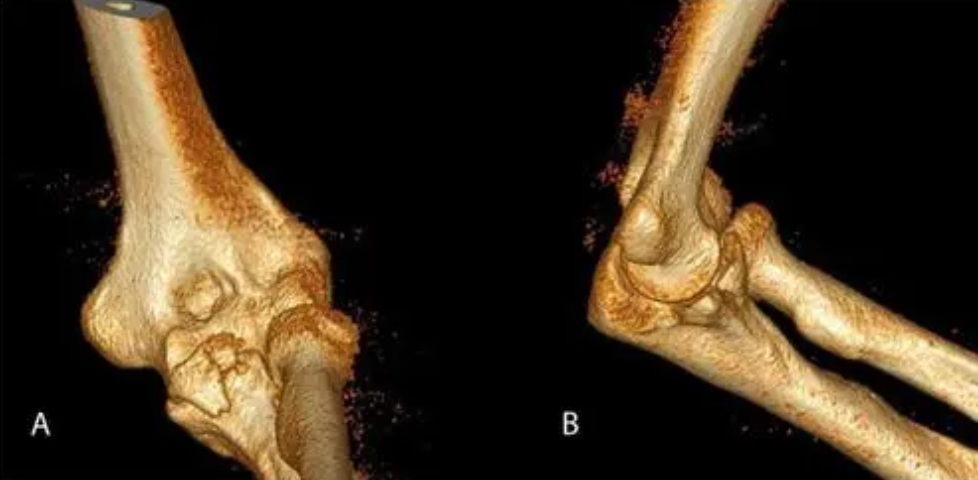

临床诊断冠状突骨折时常采用CT、X线片以及三维重建这三种影像学检查。

与CT检查和X线检查相比,三维重建在检查冠状突骨折时具有较好的优势,它不仅能够直观的看到骨折特征,还能从不同的角度来观察骨折的形态,提高了医生对冠状突骨折的分型、诊断与评估的准确性。